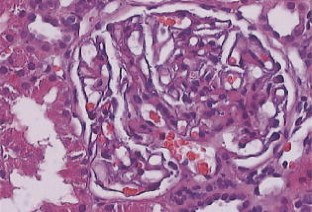

Die Lupusnephritis ist ein bekanntes Phänomen beim systemischen Lupus erythematodes (SLE). Wir untersuchten die Nierenbiopsie einer 30-jährigen Frau mit SLE. Die Anamnese zeigte einen klinisch typischen SLE mit generalisierten Symptomen mit positivem ANA- und Anti-ds-DNA-Titer ohne Nachweis von Lupuskoagulans, des Rheumafaktors, von Kryoglobulinen sowie ohne Antiphospholipid-Antikörper. Eine Paraproteinämie war weder für IgG noch für IgA oder IgM nachzuweisen. Mit Hilfe der Lichtmikroskopie, der Elektronenmikroskopie sowie der Immunelektronenmikroskopie wurden elektronendichte Ablagerungen in subepithelialer, subendothelialer und mesangialer Lokalisation nachgewiesen. Zusätzlich fanden wir sowohl in den elektronendichten Ablagerungen, als auch im angrenzenden Mesangium Kristalle eines elektronendichten Materials. Diese kristallinen Strukturen sind aus IgG und κ-Leichtketten zusammengesetzt, während IgM, IgA sowie λ-Leichtketten mittels Immunelektronenmikroskopie nicht nachzuweisen waren.

Lupus nephritis is a common phenomenon in Systemic Lupus Erythematosus (SLE). We analyzed a renal biopsy of a 30-year-old woman with SLE. The clinical history showed a typical SLE with generalized symptoms without demonstrable lupus coagulant, positive for anti-nuclear antibodies and anti-ds-DNA antibodies but negative for rheumatoid factor, cryoglobulins and antiphospholipid antibodies. A paraproteinemia for IgA, IgG and IgM was not detectable. Using light, electron and immunoelectron microscopy electron-dense deposits were noted in subepithelial, subendothelial and mesangial position. Most remarkably, the electron-dense deposits and mesangial areas in the vicinity of deposits contained an electron-dense crystalline material. The crystalline structures were composed of IgG and kappa light chains, while they were negative for IgM, IgA and lambda light chains, as demonstrated by immunoelectron microscopy.